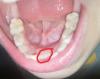

Девочки подскажите про постоянные зубы. У нас выпал первый молочный и постоянный растёт, но как то не ровно. Стоит беспокоится или он потом встанет как надо? Или лучше к стоматологу идти?

Фото в комментариях

@shepel да, похоже. Я вообще только сегодня увидела этот зуб, его не было 3 недели, после того как выпал молочный.